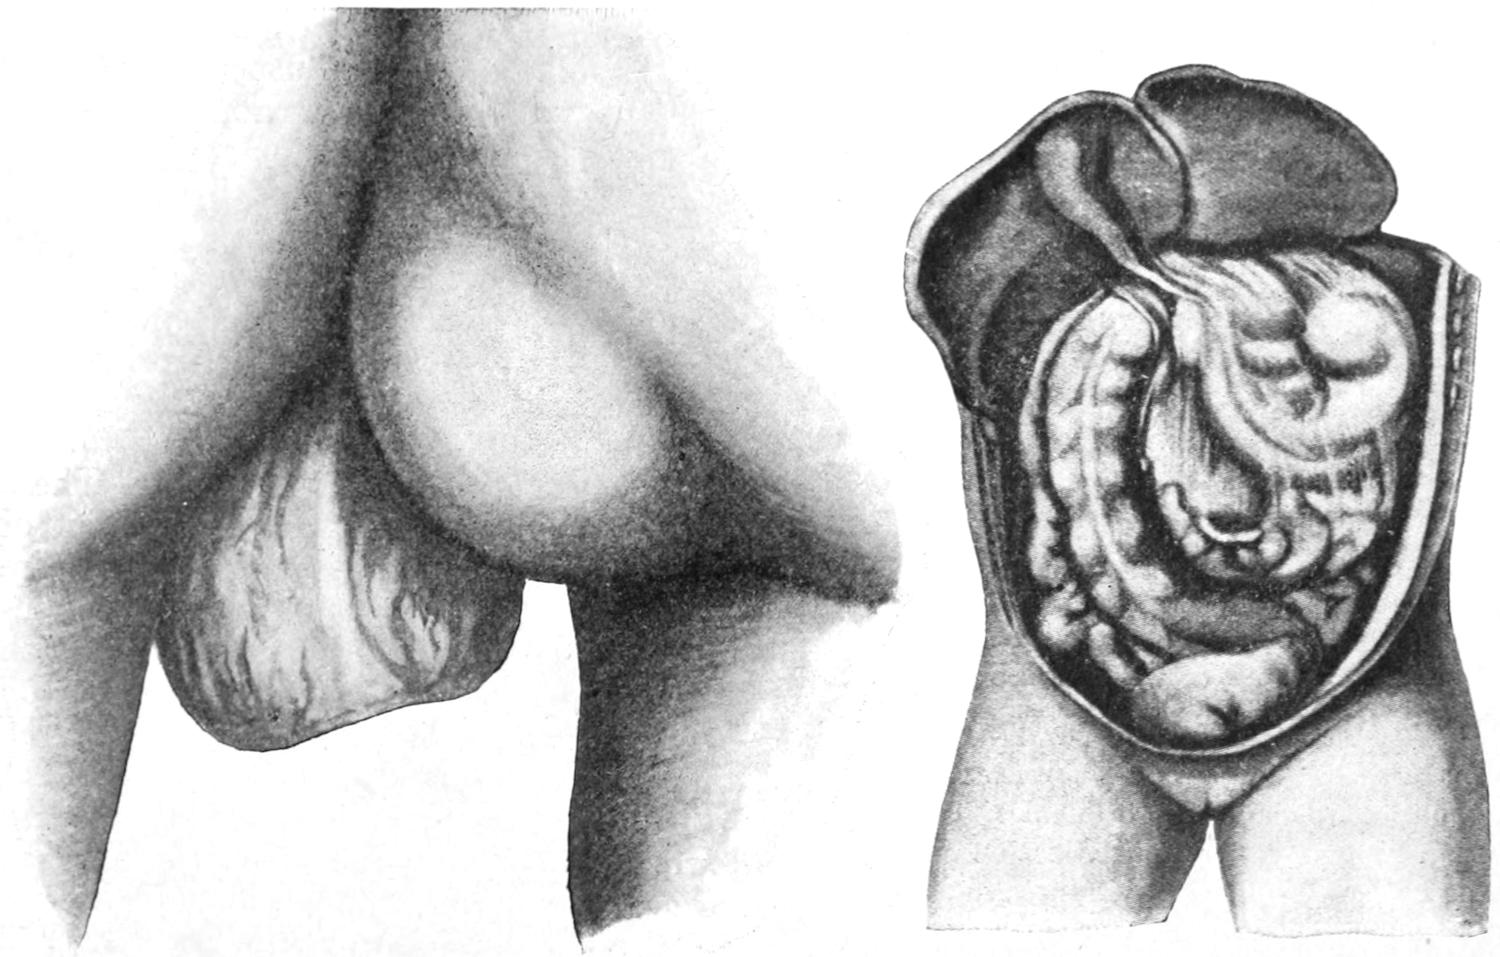

HERNIA 890